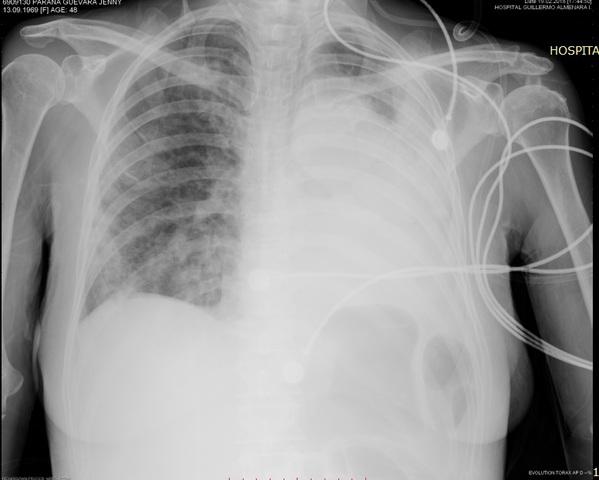

Guardia noche: Marcada dificultad respiratoria

UCE: PASE A SU SERVICIO

INICIA VASOPRESORES - SEDOANALGESIA - VM

ACTUALIZA ANALITICA, RX TORAX